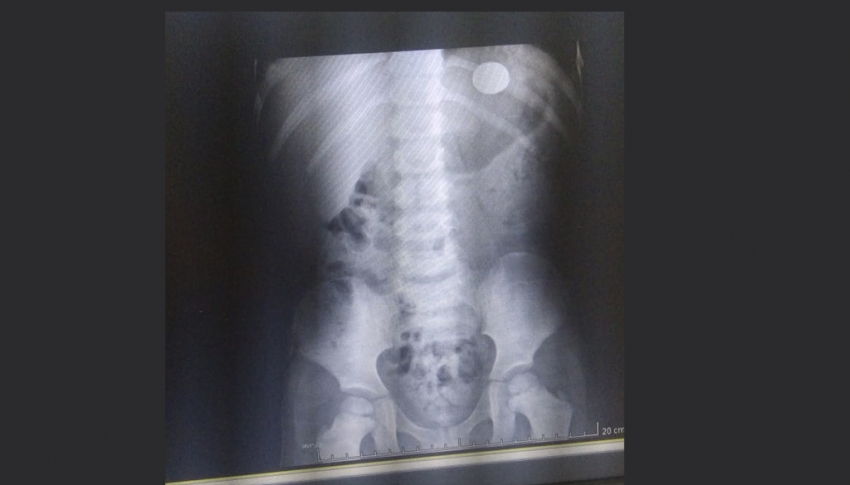

“Ele (o filho) começou a falar que estava com uma dor no coração e então eu perguntei o que tinha acontecido e ai ele contou que teria engolido a moeda e então o levamos à UPA (Unidade de Pronto Atendimento de Ourinhos) e fizemos o exame de raio X e vimos que a moeda estava em sua barriga”, contou a mãe.

O garoto engoliu a moeda no dia 9 (domingo), mas o objeto não se moveu para o intestino e se isso persistir, o menino poderá ter que passar por um procedimento cirúrgico para retirar a moeda.

Imagem da moeda engolida por menino em Ourinhos (Foto: Arquivo Pessoal)